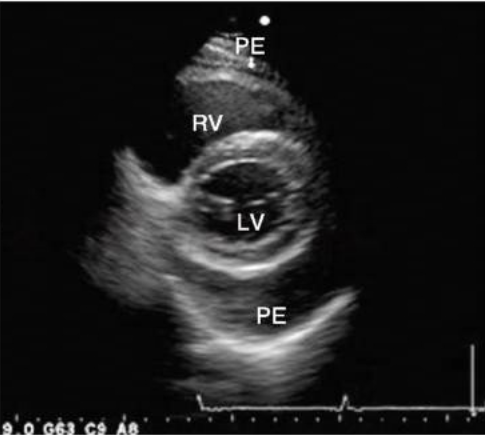

图片信息来源:胸骨旁短轴切面(PSAX)示心包积液

在某些超声切面上,胸腔积液与心包积液可能看起来非常相似,特别是在心脏后方区域,很容易造成误判。

因此在判断时,需要重点关注解剖位置(anatomical relationship),例如:积液是否位于descending aorta(降主动脉)前方,液体是否位于心包反射范围内。通过这些结构标志,可以帮助区分Pericardial Effusion与Pleural Effusion。

中量积液(Moderate effusion):

随着液体量增加,积液不再局限于左室后方,而是开始向心脏周围扩展。其典型特点包括:心脏周围多个区域均可见液体,在不同切面均可观察到液性暗区,液体宽度通常约10–20mm。此时在影像上往往可以看到 心脏被部分液体环绕,但仍未形成明显的心脏摆动。

大量积液(Large effusion):

当心包腔内液体明显增多时,液体会广泛环绕心脏分布。其主要影像特征包括:心脏周围广泛液性暗区;宽度通常>20mm;在某些情况下可出现Swinging heart sign(心脏摆动征)。当积液达到这一程度时,需要进一步关注是否出现血流动力学受压表现,并警惕Cardiac Tamponade(心包填塞)的可能。